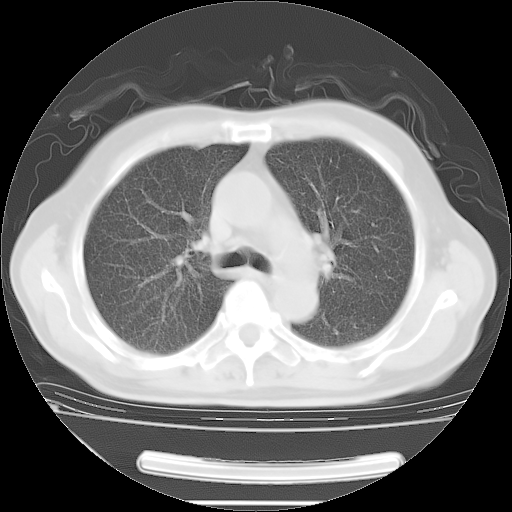

今天复查肺部CT,发现双肺广泛磨玻璃样改变。所以我把3月19日和5月9日相隔50天的肺部CT上传。请大家会诊。

5月9日肺部CT(在4月27日齐鲁医院肺部CT描述部分肺组织磨玻璃样改变,12天后肺组织广泛磨玻璃样改变)

大致读了系列胸部CT:纵隔窗无明显异常,肺窗:从4、27至今:主要是双肺中下野外带可见毛玻璃样改变,目前处于急性肺泡炎阶段,至于原因考虑1、结替组织或胶原血管性疾病所致?2、恶性疾病如恶组在肺部所致的表现或细支气管肺泡癌?3、药物或其它原因如肺蛋白沉着症所致肺泡炎目前不太可能?总之,明天就去请我院的呼吸科、感染科、血液科和临免专家会诊哈。